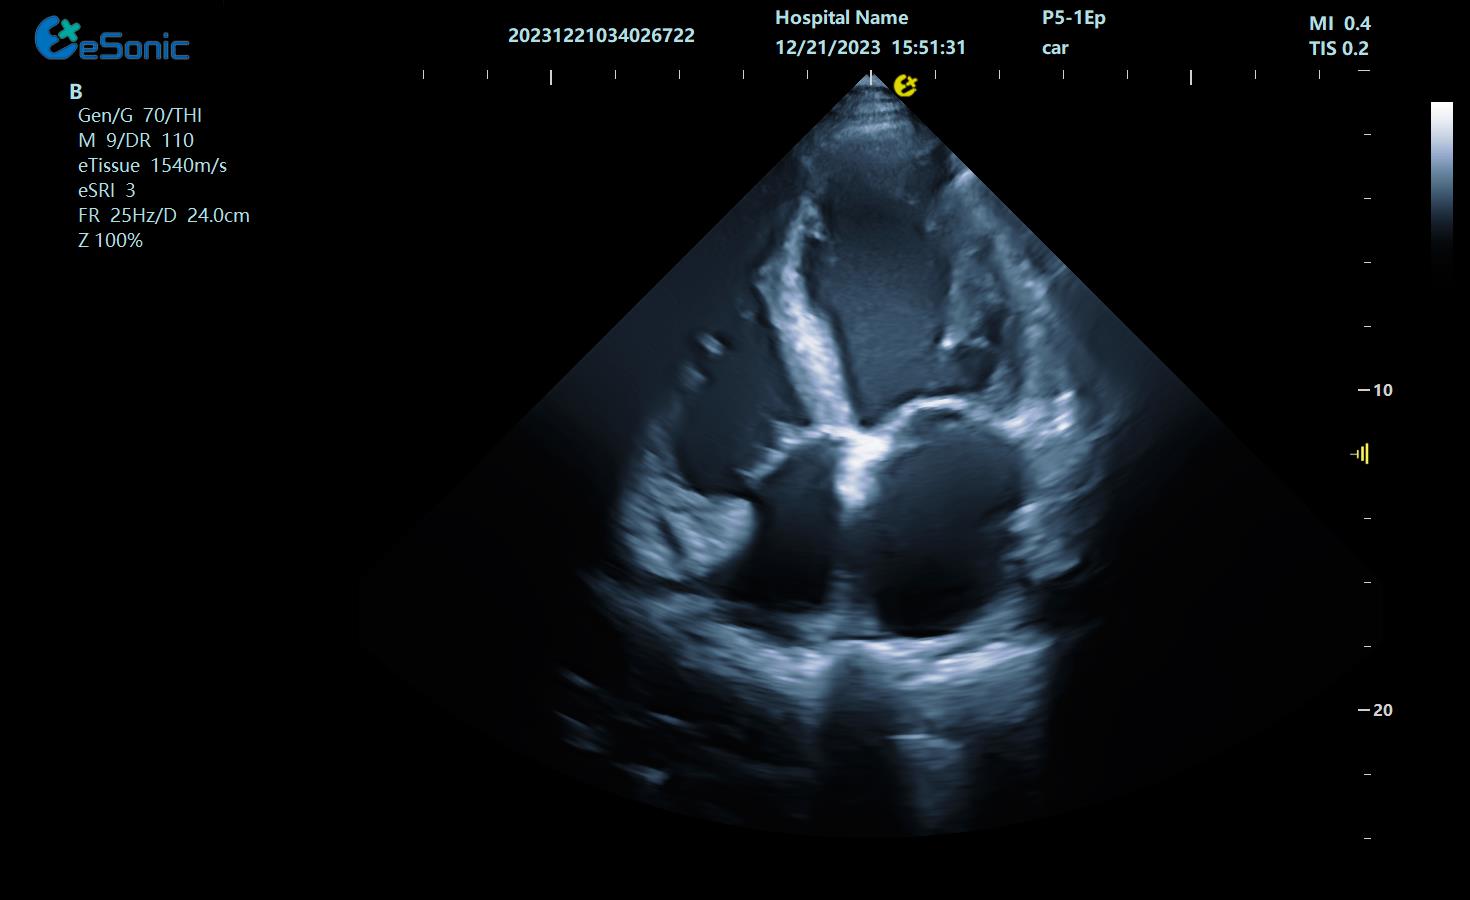

心尖四腔心

三尖瓣返流

心脏彩色M型

组织多普勒